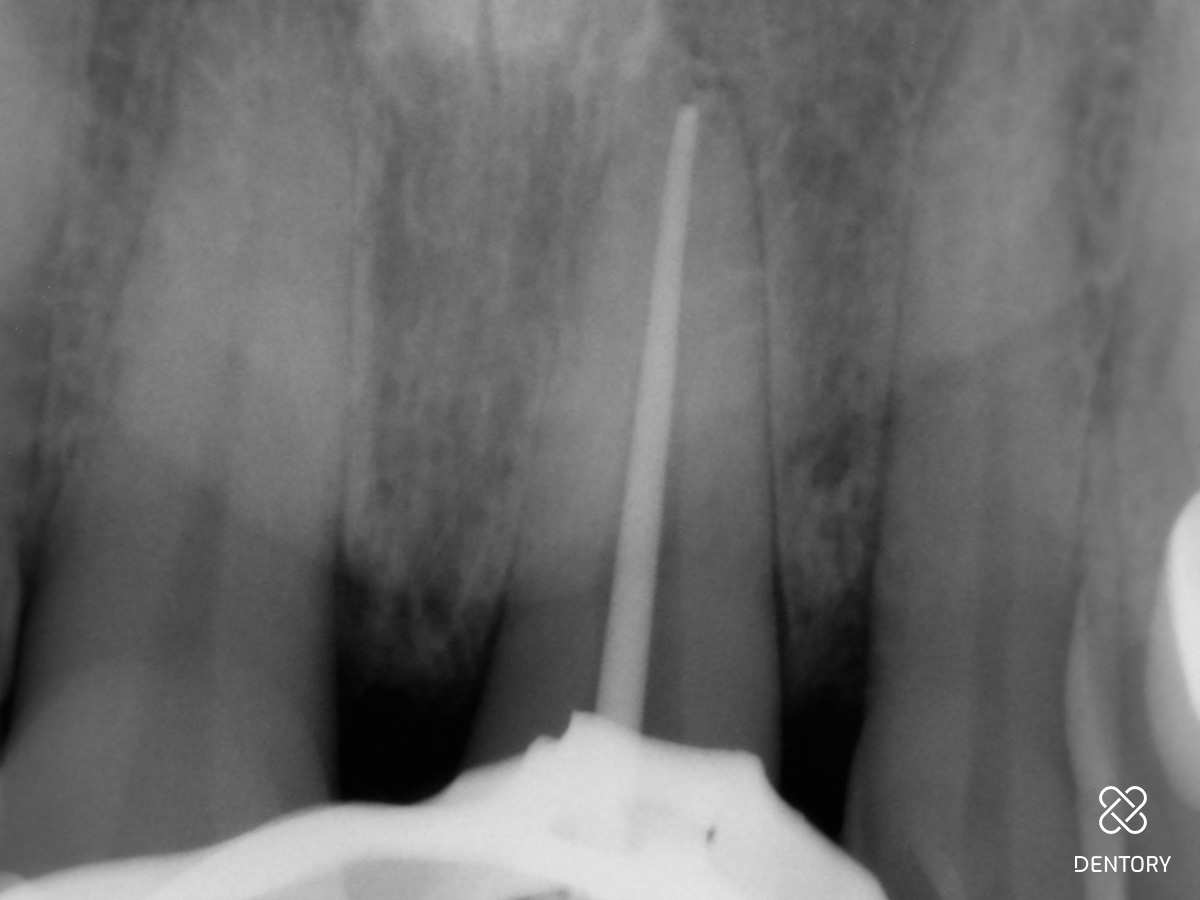

Abbildung 5

Sobald der Glasfaserstift komplett entfernt worden ist, kann mit einer Revisionsfeile weitergearbeitet werden; Sicherheitslänge: 21 mm.